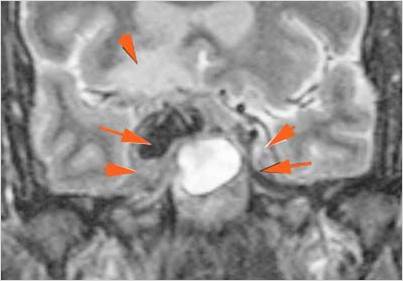

There is evidence of thrombus, thrombophlebitis or other occlusive or inflammatory process of the cavernous sinus. [Yes/No]

There is evidence of inflammation of the distal internal carotid artery. [Yes/No]

The superior and/or inferior ophthalmic veins are dilated or thrombosed. [Yes/No]